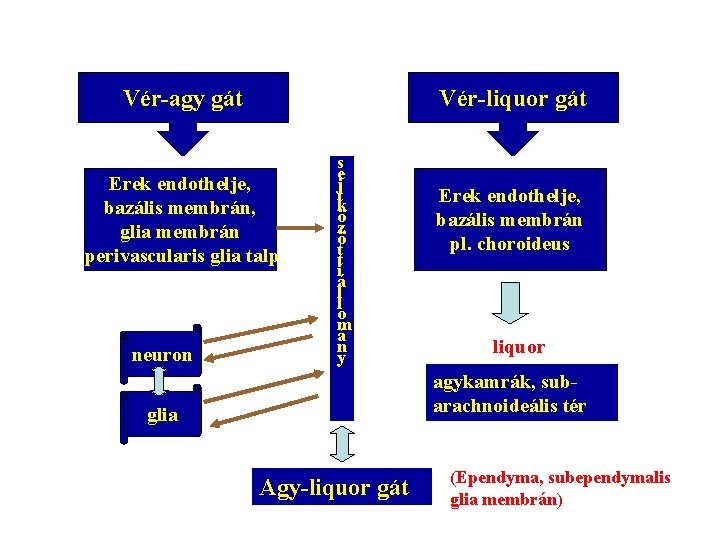

Vér-agy gát Vér-liquor gát Erek endothelje, bazális membrán, glia membrán perivascularis glia talp neuron s e j t k ö z ö t t i á l l o m á n y Erek endothelje, bazális membrán pl. choroideus liquor agykamrák, subarachnoideális tér glia Agy-liquor gát (Ependyma, subependymalis glia membrán)